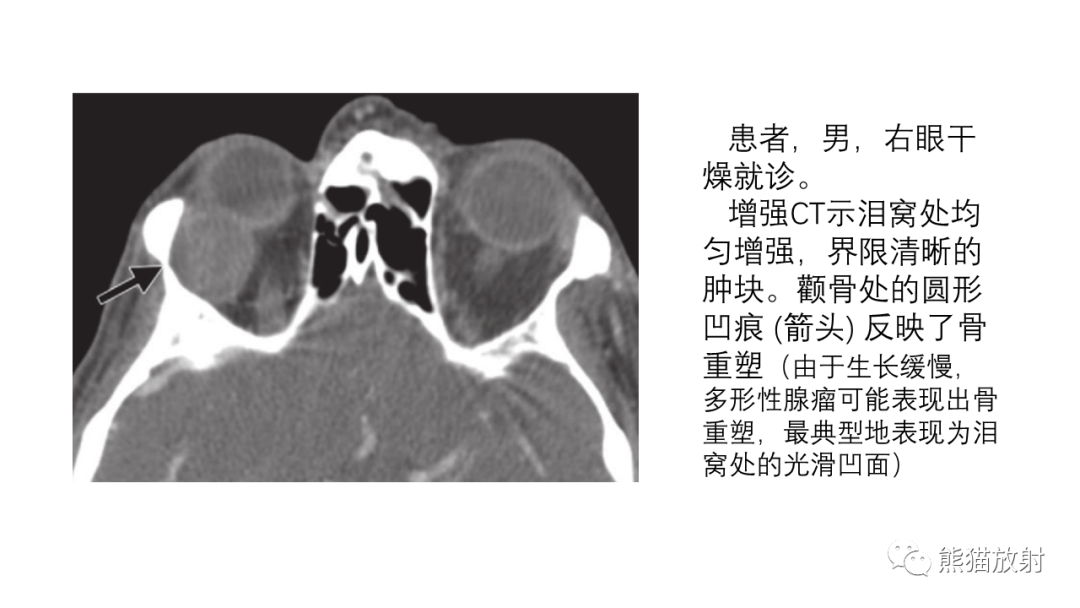

【PPT】泪腺多形性腺瘤 VS 眼眶淋巴瘤-6

【PPT】泪腺多形性腺瘤 VS 眼眶淋巴瘤-7